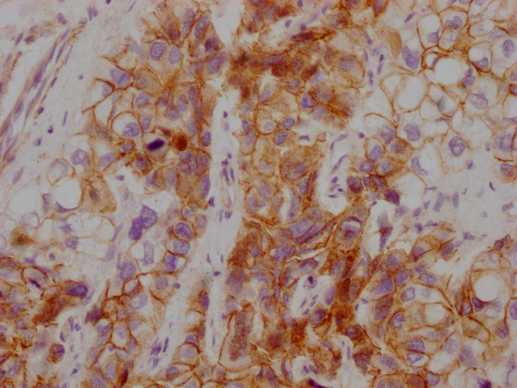

Human liver cancer

1:100